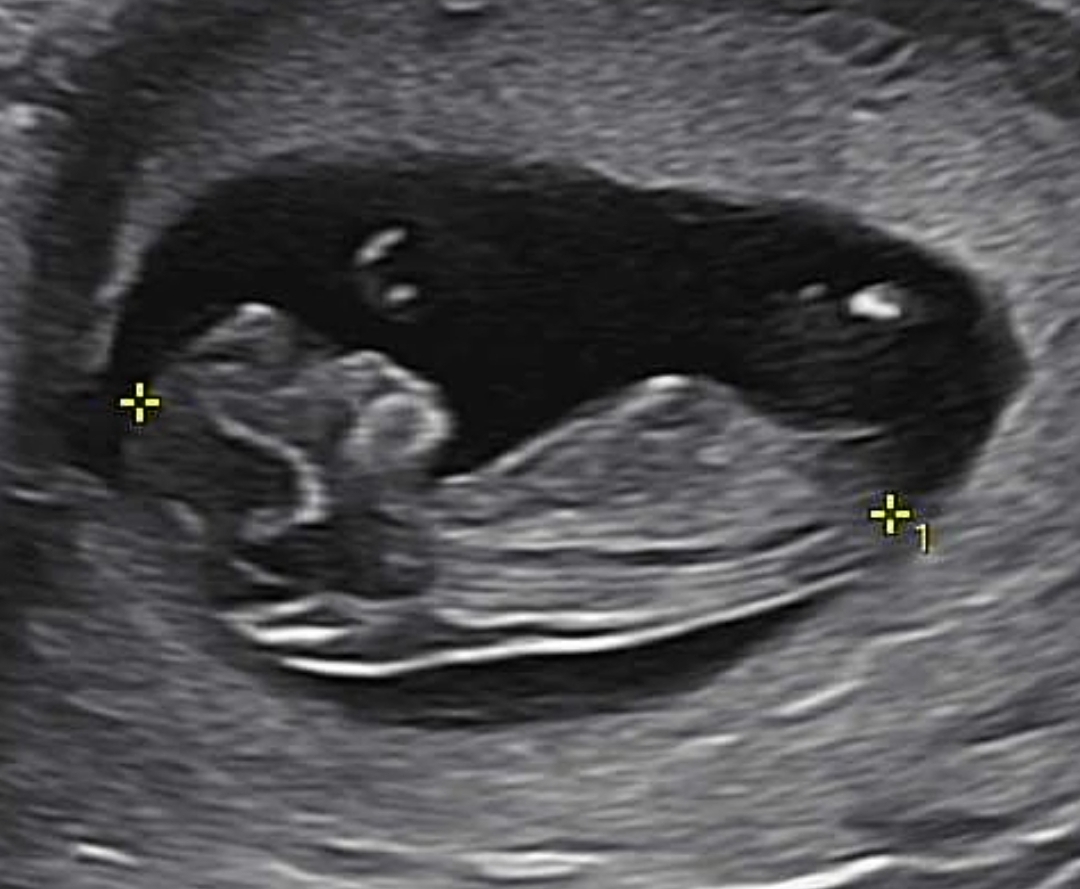

11주차 각도법 한번 봐주시겠어요?

아들이여도 딸이여도 상관없고 건강하고 튼튼한 아이로 태어나고 자랐으면 좋겠어요^^ 아직 너무 이르지만 혹시 각도법 고수분은 아실 수 있나 해서요

딸 같은데요?

이 사진까지 첨부합니다